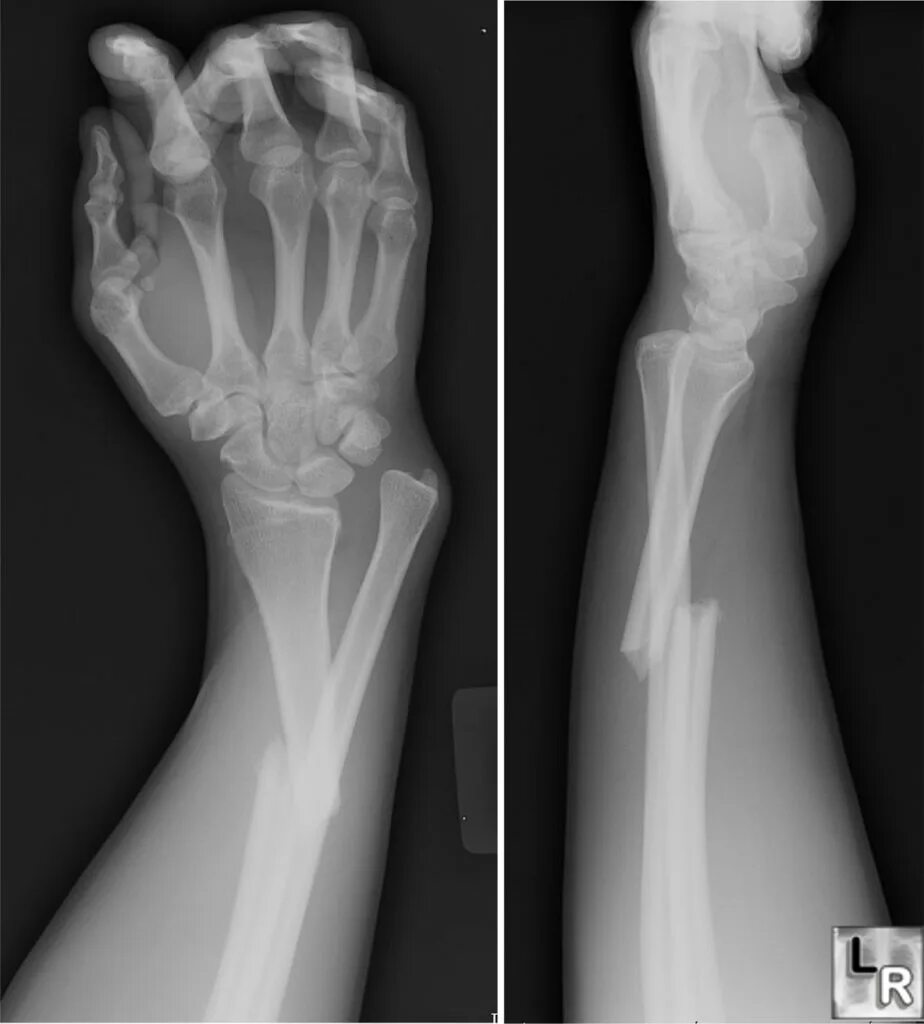

Снимок перелома со смещением